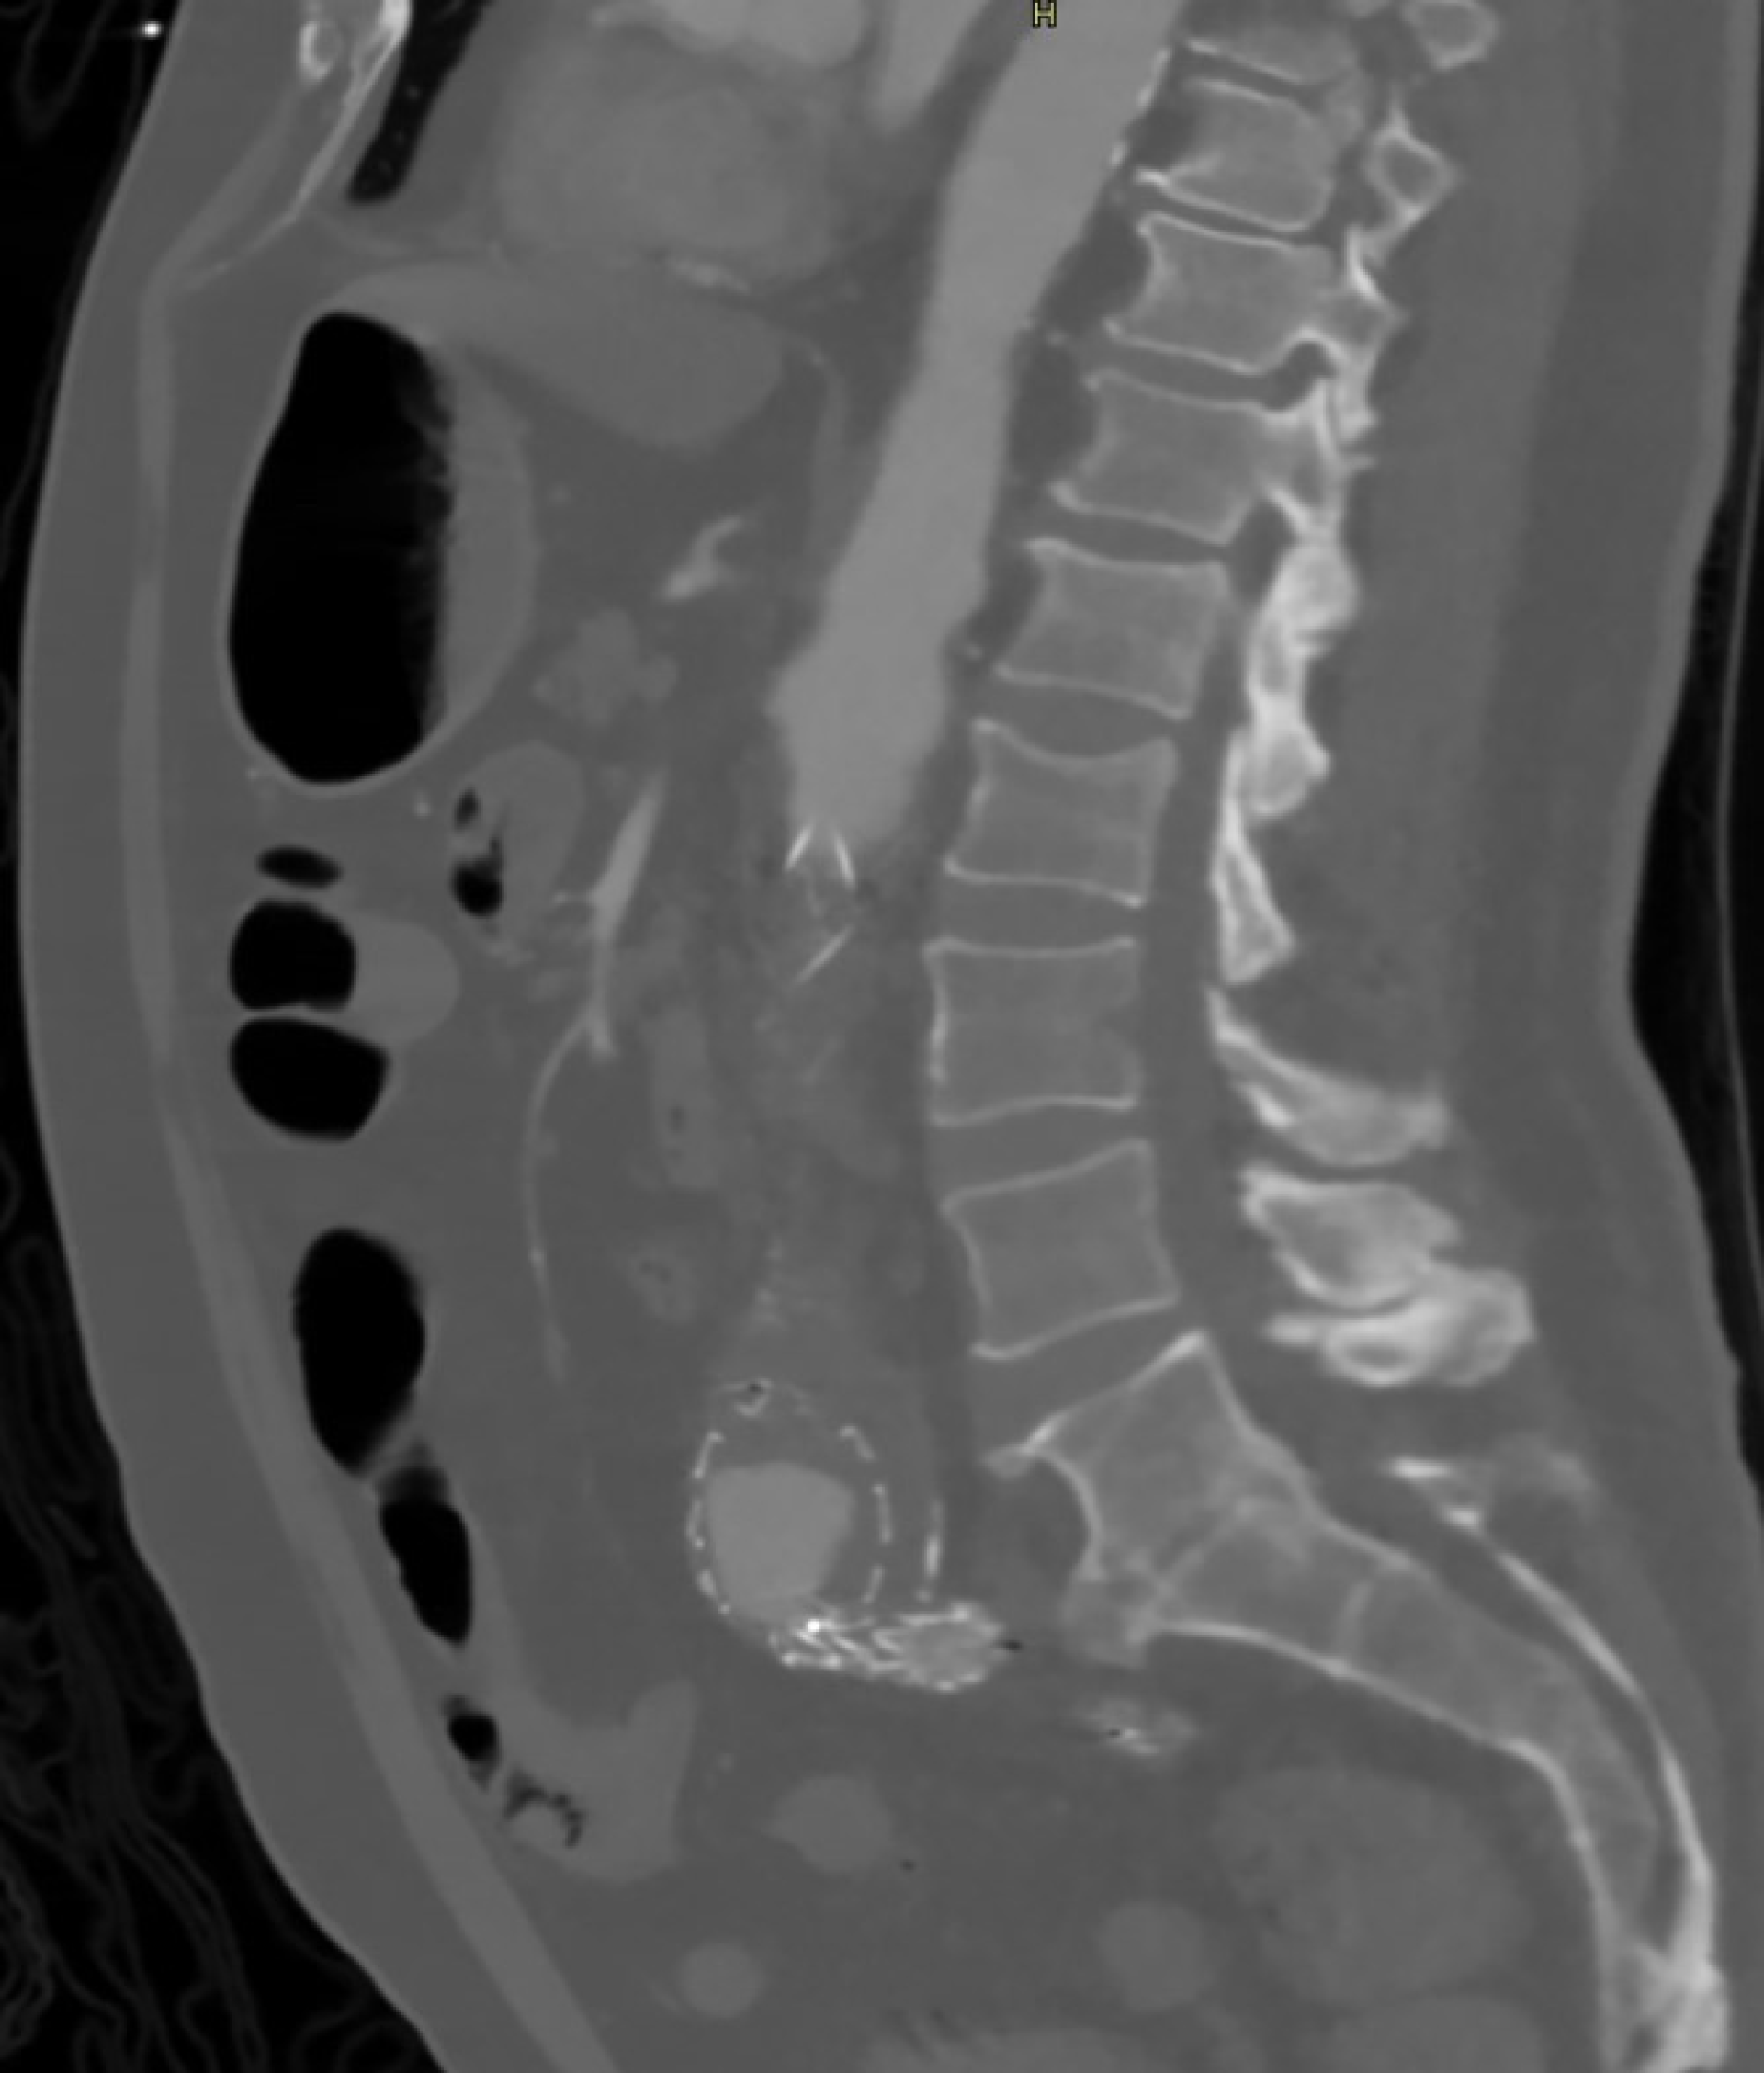

Onze casus betreft een 69-jarige zorgmijder die onder andere bekend was met een aortaprothese (EVAR), een doorgemaakte duodenumbloeding zes maanden eerder met op de destijds verrichte CT abdomen een normale wervelkolom (figuur 1) en sinds anderhalve maand toename van bekende lumbago. Door de huisarts was meermaals getracht een MRI van de wervelkolom te laten verrichten, maar patiënt was hier zowel lichamelijk als geestelijk nog niet toe ‘te mobiliseren’ geweest. Patiënt had een moeizame relatie met zijn huisarts en had over het algemeen weinig vertrouwen in hulpverleners waarmee hij frequent in conflict kwam. Er waren vermoedens op persoonlijkheidsproblematiek. Wat betreft de MRI had hij aangegeven daar niet in te durven, niet te kunnen liggen door de pijn, geen vervoer te hebben en überhaupt het nut van beeldvormend onderzoek niet in te zien. Even later werd patiënt ingestuurd naar de Spoedeisende Hulp vanwege koorts en rugpijn, alwaar bij lichamelijk onderzoek een parese van beide benen opviel. Ook bleek er sprake van urine-incontinentie waarbij er gedacht werd aan een reeds langer bestaand caudasyndroom. Laboratoriumonderzoek toonde verhoogde inflammatieparameters (bezinking 91 mm/uur; CRP 267 mg/l) en op een MRI van de wervelkolom werd een uitgebreide spondylodiscitis van L1 t/m L3 gezien met werveldestructie en abcesvorming (figuur 2). Uit urine-, bloed- en latere peroperatieve kweken werd een ESBL E. Coli geïsoleerd. Patiënt kreeg boomstamverpleging en werd met meropenem en pijnstilling behandeld. Met als doel patiënt weer enige mobiliteit, vermindering van pijn en verbetering van kwaliteit van leven te kunnen bieden, werd besloten de lumbale wervelkolom te stabiliseren door middel van percutane fixatie middels schroeven en staven. Hierop had patiënt weliswaar meer bewegingsvrijheid, maar zijn krachtsverlies en slechte conditie waren dusdanig invaliderend dat hij zijn bed alsnog niet uitkwam. Verder persisteerde de koorts ondanks reeds meerdere weken intraveneuze antibiotische therapie. Er werd een PET-CT verricht ter evaluatie van eventuele betrokkenheid van de nabijgelegen EVAR. Dit leek niet het geval; wel was er sprake van een zich verder uitbreidende infectie. Na uitvoerig multidisciplinair overleg met collega’s van de geriatrie, orthopedie, neurologie, microbiologie, radiologie en infectiologie en vervolgens een second opinion in het academisch ziekenhuis bleek een tweede, zeer ingrijpende operatie vereist om de uitgebreide spondylodiscitis verder te behandelen.

Figuur 1. Sagittale CT abdomen van zes maanden vóór presentatie met normaal aspect van de lumbale wervelkolom